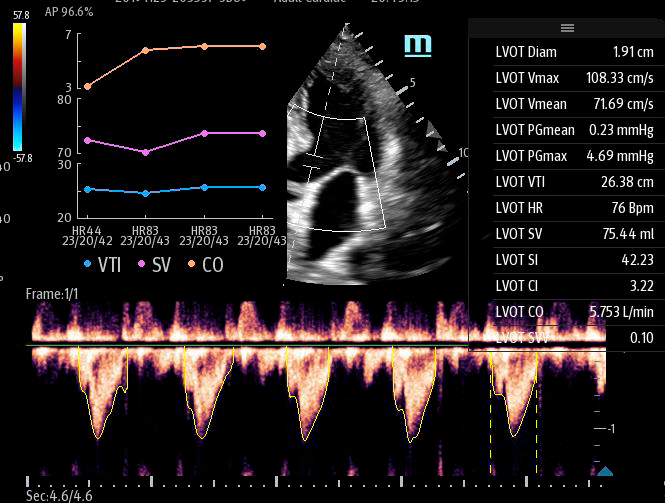

Чтобы использовать уравнение, нужно получить поток выносящего тракта левого желудочка в PW допплере — это достаточно кропотливая работа. В ультразвуковых системах Mindray Resona i9 эта задача решается автоматической оценкой потока выносящего тракта – Smart VTI.

Доктору остается получить 5-ти камерное сечение сердца и нажать одну кнопку на сенсорном экране. Прибор сам выберет расположение контрольного объема, получит спектрограмму и обведет спектр с расчётом всех показателей. Быстро и эффективно.